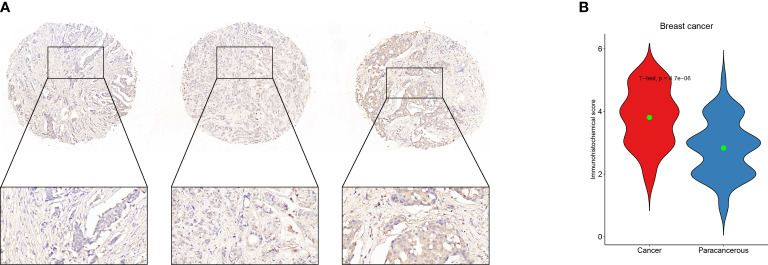

Definition of hub genes and immunohistochemistry verification

In order to get the hub gene, the IFN- genes were imported into the Cytoscape program, and then a PPI network diagram was created. The proteins are denoted by the nodes, whereas the strength of the association between these proteins is denoted by the links. As can be seen, there are a total of 19 nodes in the PPI network, as well as 92 connections. The STAT1 gene is deemed to be the hub gene since it has the greatest degree of association (f6). By means of IHC, we compared the expression of STAT1 in breast malignancies and paracancerous tissues and found that STAT1 was considerably overexpressed in the malignant breast tissues (f7, P=4.7e-6), which was in line with the findings of our investigation.